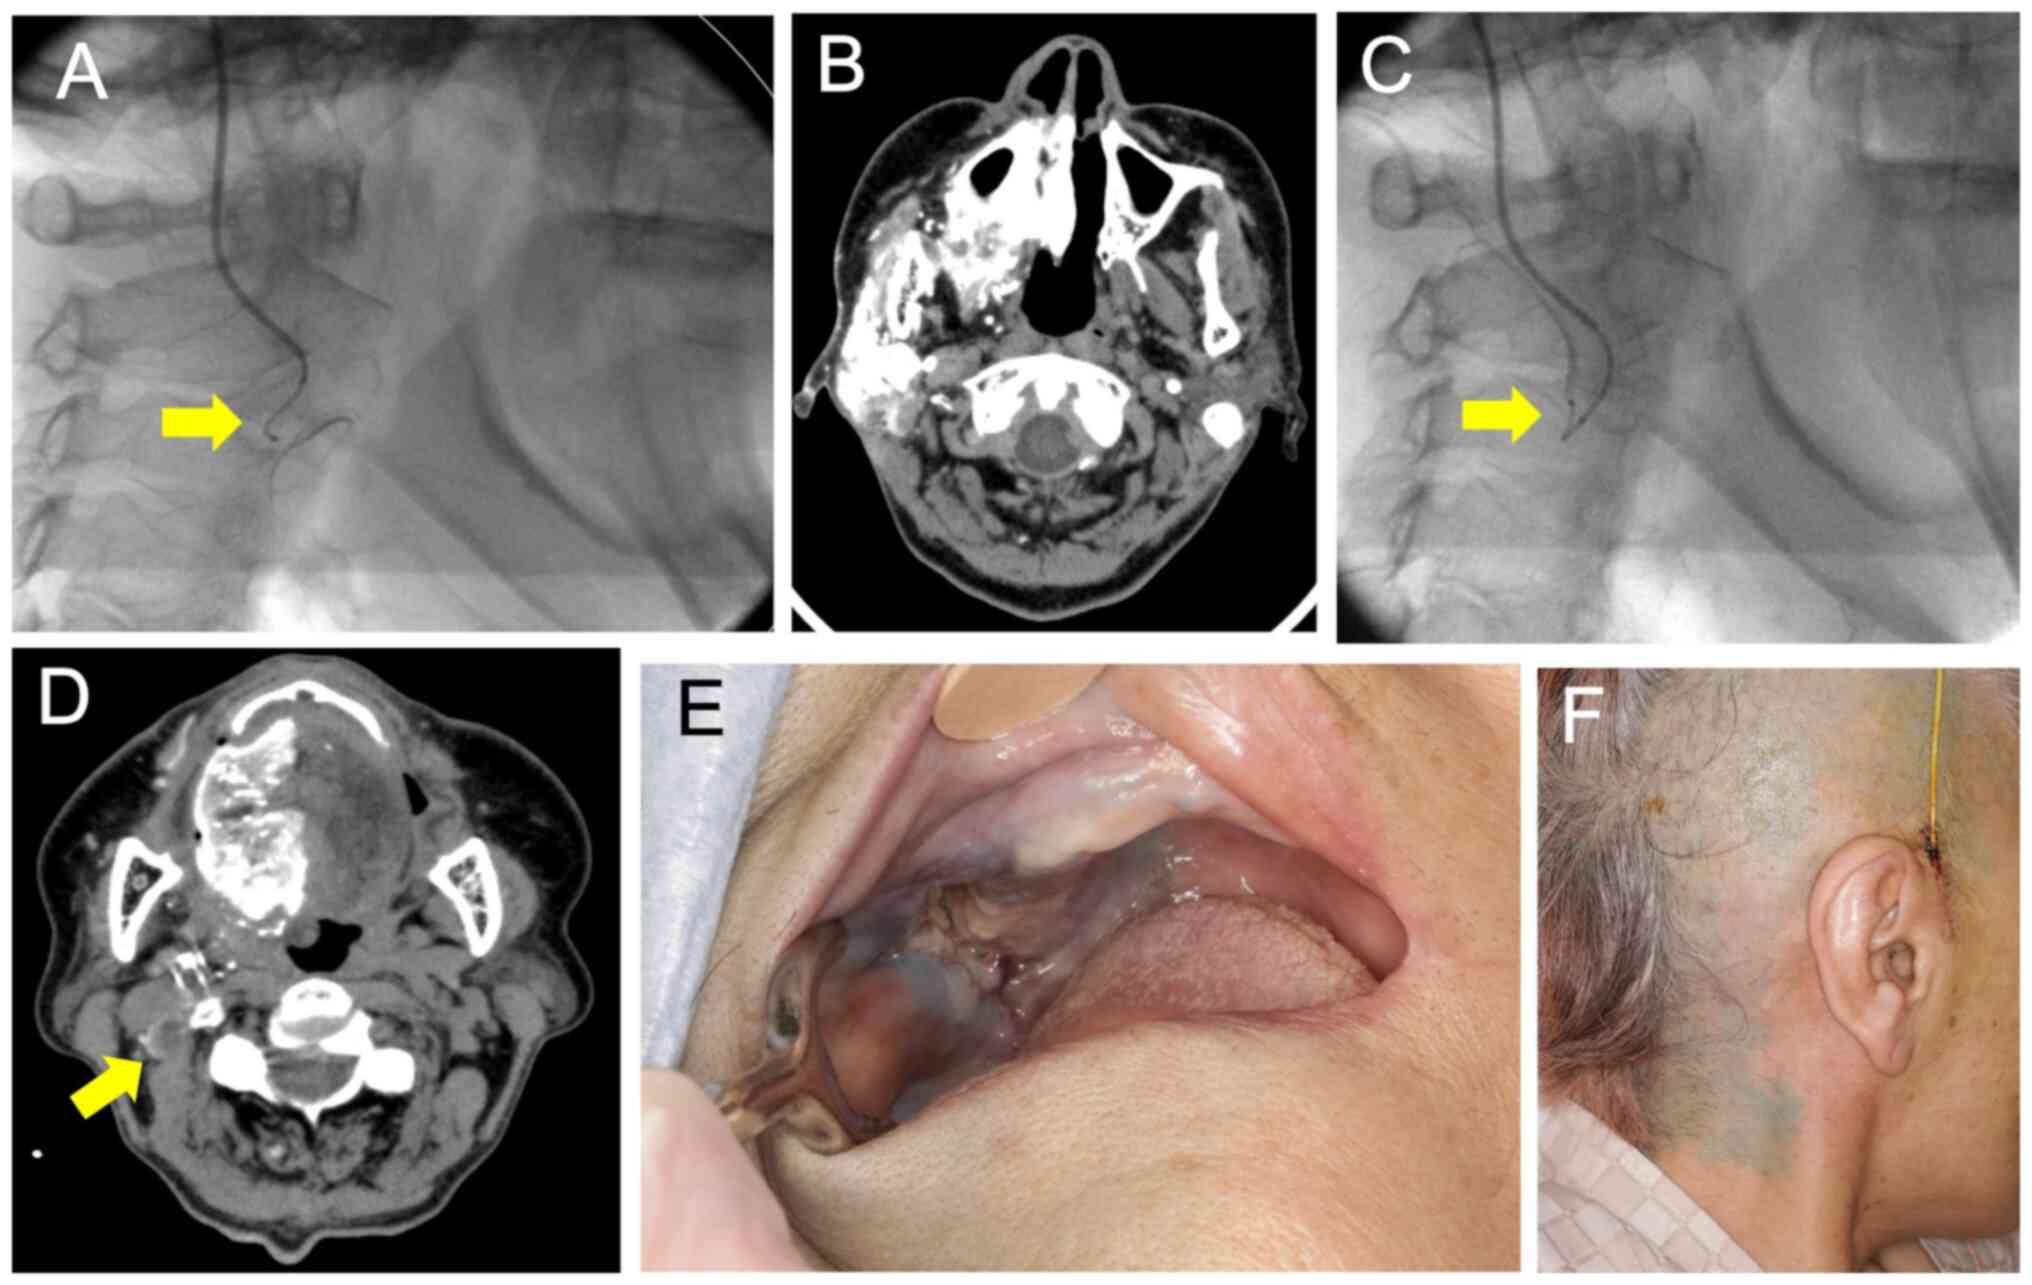

The ECAS system can superselectively administer anticancer drugs to numerous feeding arteries from the superficial temporal artery: A case report and literature review

Superselective intra‑arterial chemoradiotherapy (SSIACRT) is one of the curative treatments for advanced oral cancer. SSIACRT can reportedly treat cervical lymph node metastases in the level I‑IIA area by super selectively catheterizing the facial artery (FA) and infusing drugs. However, since advanced oral cancer lesions involve a number of feeding vessels, retrograde treatment requires the placement of catheters from the superficial temporal artery (STA) and occipital artery (OA). Furthermore, in the case of level IIB lymph node metastasis, the catheter must be changed because it is necessary to administer anticancer drugs to more than three routes, including the OA, when the feeding arteries of the primary tumor are combined. The external carotid artery sheath (ECAS) system used in the present study involves the insertion of a microcatheter or steering catheter from one route of the STA, allowing selection of numerous feeding vessels, including the OA. The ECAS system can facilitate the administration of chemotherapy via the STA simultaneously to the maxillary artery, lingual artery, FA and OA. The present study describes cases of maxillary gingival cancer and tongue cancer with cervical lymph node metastasis, which were treated with the ECAS system via the STA; the treatment successfully controlled both the primary tumor and cervical lymph node metastasis. In the two cases described in the present study, metastatic lymph nodes were found in the level ⅠB and ⅡB region, but were successfully treated by administering cisplatin via the OA, in addition to the primary lesion. To date, to the best of our knowledge, there is no case report clearly referring to the treatment of lymph node metastasis using the ECAS system. In conclusion, SSIACRT using ECAS may be considered a useful treatment for oral cancer with cervical lymph node metastasis.